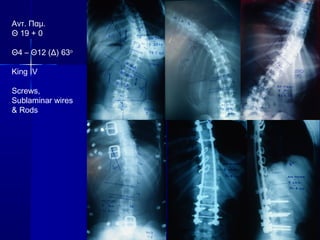

47. 49. 50. 51. 52. 53. 54. 55. Αντ. Παμ.

Θ 19 + 0

Θ4 – Θ12 (Δ) 63ο

King IV

Screws,

Sublaminar wires

& Rods